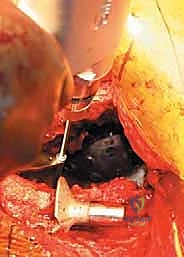

هذه من أخطر المراحل. يجب إزالة الكوب القديم، والبراغي، والأسمنت الطبي بدقة وحذر شديدين لتجنب إحداث المزيد من الدمار في العظم المتبقي أو إصابة الأوعية الدموية المجاورة. يستخدم الدكتور هطيف أدوات دقيقة متخصصة (مثل الأزاميل المرنة والمناشير الدقيقة) لفصل المفصل عن العظم.

4. تنظيف العيب العظمي وتحضيره (Debridement)

بعد إزالة المفصل، يظهر حجم الكارثة العظمية. يقوم الجراح بتنظيف التجويف الحقي من جميع الأنسجة الليفية، والندبات، وبقايا البلاستيك والمعدن، والعظم الميت. الهدف هو الوصول إلى عظم حي ينزف دماً، وهو شرط أساسي لنجاح الترقيع العظمي.